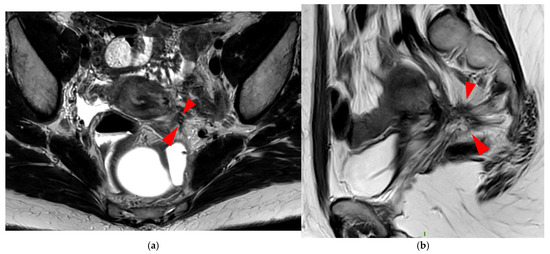

A type 6 USL is associated with adjacent pelvic “visceral” involvement in a broad sense. It most commonly affects the digestive tract (Figure 8 and Figure 9), with the rectum and rectosigmoid junction wall thickening: in this case, the lesion often appears as a “medallion-shaped” protrusion into the lumen. Less frequently, the urinary tract is affected (Figure 9 and Figure 10), involving the muscular layer of the bladder or even the distal ureter at the level of the common iliac artery, with stenosis potentially leading to upstream hydronephrosis. More rarely, as USLs are also close to nearby pelvic nerve structures (Figure 11), contiguous involvement of the inferior hypogastric plexus located in the sacro-recto-genital septum (a.k.a. Delbet sagittal fascia) beneath the distal two-thirds of the USL, or exceptional involvement of the sciatic nerve adjacent to the pelvic wall, is possible (Figure 12, Figure 13 and Figure 14).

Figure 8. Pelvic MRI scan of a patient with HTD type 6 USLs. (a) Axial T2WI shows a thick (3 mm) right USL (arrowhead) with regular margins, initially classified as a type 3A USL; the left USL is not visible (type 1). (b,c) Coronal (b) and sagittal (c) T2WI show sigmoid colon wall infiltration appearing as a “medallion-shaped” lesion (arrows). The presence of “visceral” involvement of the digestive tract leads to the reclassification of these USLs as type 6.

Figure 12. Pelvic MRI scan of a patient with a HTD type 6 left USL. (a,b) Axial (a) and sagittal (b) T2WI show a spiculated nodular hypointense lesion (arrowheads) extensively involving the left inferior hypogastric plexus contained within the sacro-recto-genital septum, as well as its afferent and efferent nerve fibers.